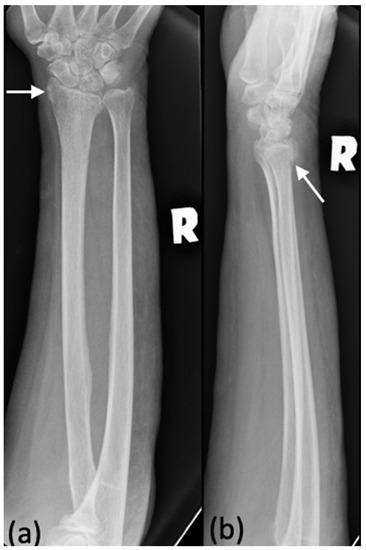

Figure 1. (a,b) An example of a radiograph categorized as a minor discrepancy. This right forearm radiograph was performed on a 25-year-old male who presented with pain after a sports injury. Both the trainee and radiologists agreed that this patient had a fracture of the distal end of his radius. However, the trainee did not report the angulation and dislocation, shown in (b) (white arrow).